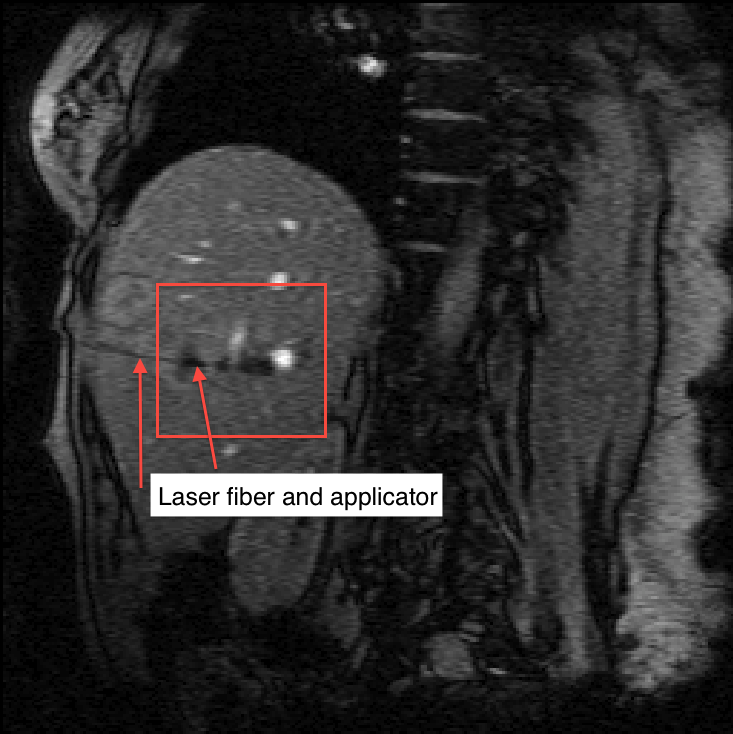

Refer to caption

(a) Magnitude image

Figure 3: Magnitude and phase of a gradient echo pulse sequence during thermal therapy. The heating causes signal loss in the magnitude image and a shifted phase in the phase image. The phase change due to heating and phase wrapping artifacts are pointed out. The images of Figure 4 are zoomed to the box indicated in (a). Panels (c) and (d) show the magnitude of the jump function of (b) computed using eq. (6) with a first and third order kernel. The first order edge detection clearly shows a residual background shading on the top of the liver, while the third order detector does not show the shading. The phase wrapping jumps in (c) can be easily removed by projecting the jump function to an interval of [π,π)𝜋𝜋[-\pi,\pi), which was done in (d).

For temperature imaging, complex valued 2D images are collected using a gradient echo pulse sequence. Acquisition parameters: Spoiled gradient recalled sequence, B0=1.5Tsubscript𝐵01.5𝑇B_{0}=1.5T, TR=27ms𝑇𝑅27𝑚𝑠TR=27ms, TE=12ms𝑇𝐸12𝑚𝑠TE=12ms, Pixel Bandwidth 280Hz280𝐻𝑧280Hz, Matrix 256×128256128256\times 128.

Figure 3(a) and (b) shows the magnitude and phase of the acquired image during a laser induced thermal therapy. The dark regions inside the box cause a signal loss due to the heating. At the corresponding location in the phase image a negative shift of the phase due to the heating can be seen. This shift is linear with temperature change and is used to measure temperature changes. The phase variations outside the heating zone are off resonance effects from an in-homogeneous B0subscript𝐵0B_{0} field, i.e. ΦbsubscriptΦ𝑏\Phi_{b}. The jumps (white to black) are due to phase wrapping artifacts. In Panels (c) and (d) two jump function approximations of the phase image computed using (6) with a kernels of order one and three are shown. Similar to the example in Figure 2 the first order jump function approximation is non-zero in areas of large gradients. If the first order approximation is used in (7), then the reconstructed image shows the same background that original phase image has. On the other hand, if the third order approximation is used in (7), then the resulting reconstruction has a suppressed background phase. The parameter λ𝜆\lambda in (6) is used to suppress noise and to force a sparse jump function approximation. Note that (d) is significantly more sparse than (c). For this and all other experiments in this paper λ=106𝜆superscript106\lambda=10^{-6} was used.